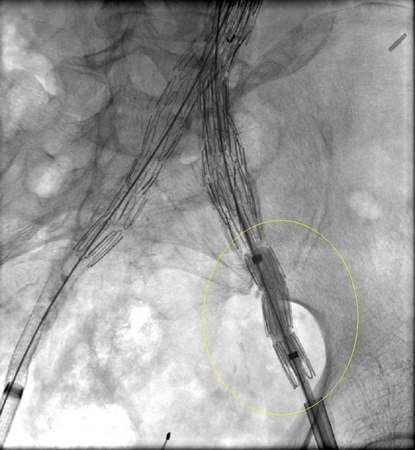

Debe hacerse todo lo posible para reparar la fuga interna de tipo I antes de completar el procedimiento (p. ej., moldeado con balón de la zona de sellado proximal, colocación de un manguito proximal, endostaples, embolización líquida).[248] Para los pacientes con un sellado proximal comprometido después de la reparación endovascular del aneurisma aórtico abdominal, se debe considerar la extensión proximal con dispositivos fenestrados y ramificados.[2] La endofuga persistente de tipo IA puede requerir la conversión a reparación abierta, siempre que el riesgo quirúrgico sea aceptable.[2][77][249][Figure caption and citation for the preceding image starts]: Extensión de endoprótesis expandida para la misma endofuga tipo I (marcada con un círculo)University of Michigan, específicamente los casos del Dr. Upchurch que reflejan los Departamentos de Cirugía Vascular y Radiología [Citation ends].

[Figure caption and citation for the preceding image starts]: Resolución de la endofuga tipo I, resuelta con la expansión de la extensiónUniversity of Michigan, específicamente los casos del Dr. Upchurch que reflejan los Departamentos de Cirugía Vascular y Radiología [Citation ends].